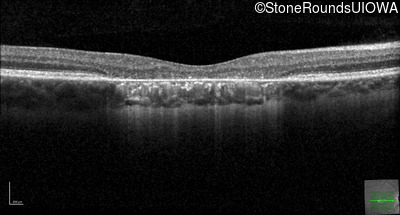

This 22 year old man had macular abnormalities noted incidentally at a routine eye exam at age 19. Since then, he has experienced a gradual loss of acuity particularly in the left eye.